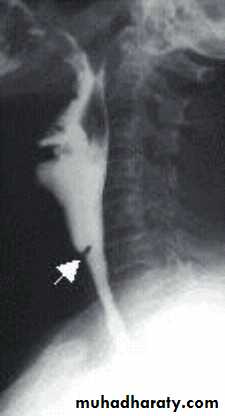

Ba-swallow: web at the postcricoid region.

Oesophageal web